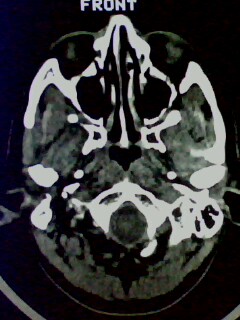

以下是引用随光逐影在2009-5-20 19:22:00的发言:[br]1)考虑左上颌骨近中线区含牙囊肿。2)鼻中隔右突偏曲。3)双侧下鼻甲肥大。